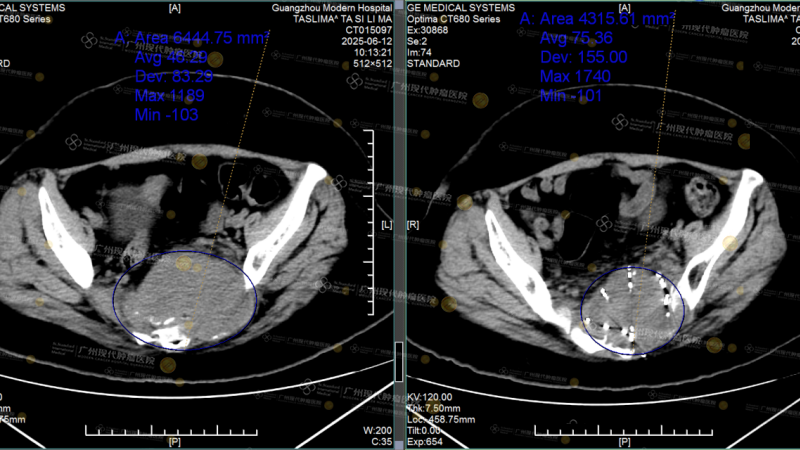

Đồng thời, bác sĩ còn phối hợp sử dụng thuốc nhắm trúng đích nhằm kiểm soát tiến triển của bệnh và duy trì trạng thái toàn thân. Theo thời gian, mỗi lần tái khám chẩn đoán hình ảnh lại mang đến một tin tốt hơn: khối u dần thu nhỏ, bên trong bắt đầu xuất hiện tình trạng hoại tử. Những thay đổi ấy khiến cả gia đình chúng tôi cảm thấy yên tâm hơn rất nhiều.

Hình ảnh CT trước và sau điều trị

Sau khi cẩn thận xem lại những hình ảnh kiểm tra mới nhất của em, bác sĩ đã đưa ra một kết luận vừa vững chắc vừa nhẹ nhàng: đánh giá hiệu quả điều trị đạt mức thuyên giảm một phần (PR).